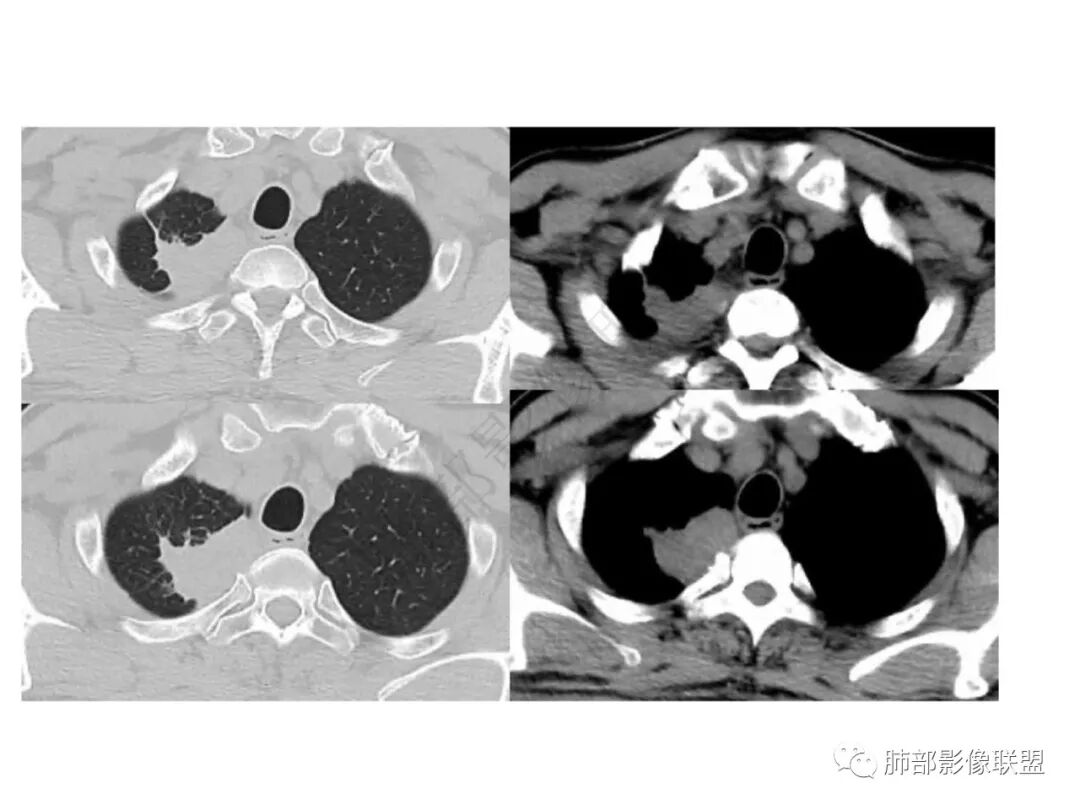

红星:老年男性患者有长期的吸烟的病史,临床症状是干咳。影像学表现右上肺胸膜下的分叶状的结节,密度欠均,内部见小灶性的坏死以及支气管空泡征,增强扫描呈明显的强化,从重建的图像来看,病灶的上下径较长,并沿着支气管的长轴生长,纵隔内无明显的肿大淋巴结。考虑肉芽肿性病变,结核性病变?炎性?鉴别诊断:肺鳞癌。

衡妈:老年男性,右肺上叶尖段沿支气管走形片状实性密度,平扫密度相对均匀,横断面显示有明显平直、凹陷边,与周围肺野界限清晰,少许长软毛刺,与侧胸膜宽基底相连,未见明显支气管堵塞;增强后明显延时强化,强化不均匀,可见小灶性坏死,所见纵隔未见肿大淋巴结。考虑慢性炎性病变,炎性肌纤维母细胞瘤?鉴别腺癌。

琦遇:病灶沿右肺上叶尖段走形实变,远端大近端小,边缘平直收缩为主,近端尖段分支部分截断,内部可见扩张的支气管粘液栓,增强后明显强化,比较均匀,内部血管走形自然,与纵膈胸膜及后胸膜呈糊墙样,未见栽桩,纵膈未见明显肿大淋巴结 综合分析考虑炎性病灶可能性大 (IMT、OP、结核、慢性炎症) 因患者年龄大、老烟民 警惕恶性可能(淋巴瘤、鳞癌) 临床上下一步做支气管镜看看

谢加平:右肺上叶尖后段见长斑块实变影,边缘清楚,有平直征,渐进性明显强化及分布血管影自然,肿块内见连续未强化粘液栓,肺门侧引流支气管征,相应肺段支气管内壁环形增厚(肉性特点),肿块周边索条纤维化,及胸膜反应性增厚,综合方向炎性肉芽肿,常规抗炎诊断两周复查,注意结核性肉芽肿,建议支气管镜肺泡灌洗及肺穿刺活检。

小锁:老年男性,急性呼吸道症状,刺激性咳嗽10天。影像:病灶沿支气管血管束走形,边缘平直收缩为主,由外向内病变,与纵膈胸膜及胸膜呈糊墙样,疑似栽赃,增强后快速明显强化,比较均匀,内部血管走形自然,内坏死灶周围环形强化,考虑炎性病灶可能性大 ,鉴别恶性肿瘤